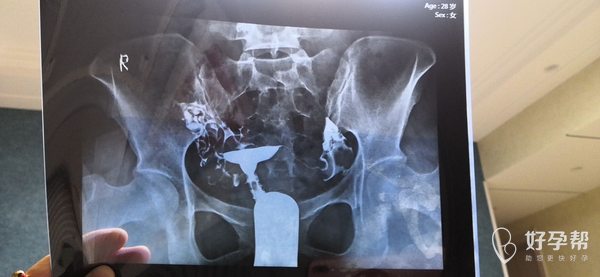

麻烦帮我看看有什么问题该做什么治疗谢谢了

你好,你的输卵管伞端上举明显,在上面就会出现拾卵障碍,可以做腹腔镜处理输卵管,也可以直接做试管,具体的要看你的年龄、卵巢功能